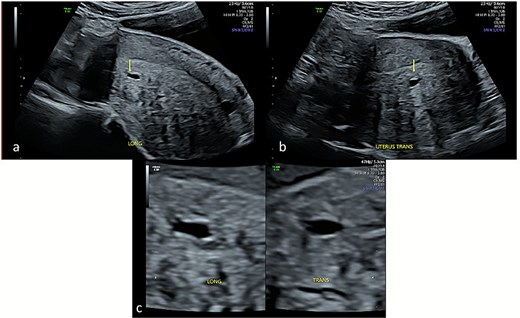

She underwent laparoscopic uterine wedge resection and bilateral salpingectomy. On entering the peritoneal cavity, the unruptured ectopic pregnancy was clearly visible (Fig. 4a and b). Intramyometrial vasopressin (4 IU) and intravenous tranexamic acid (1 g) were administered. The interstitial pregnancy was excised using a Harmonic scalpel. The myometrial defect was closed with barbed suture and the serosa with interrupted polyglactin (Fig. 4c and d). Her recovery was uneventful, and she later conceived an intrauterine pregnancy with assisted reproduction.

Laparoscopic views of the interstitial ectopic pregnancy. Part A and B demonstrate the pregnancy arising off the interstitial segment of the right fallopian tube at different magnifications, after entry into the peritoneal cavity. Part C is a progress image of the uterus after a unilateral salpingectomy and wedge resection. Part D is a progress image of the uterus after it was closed with a barbed v-lock suture.